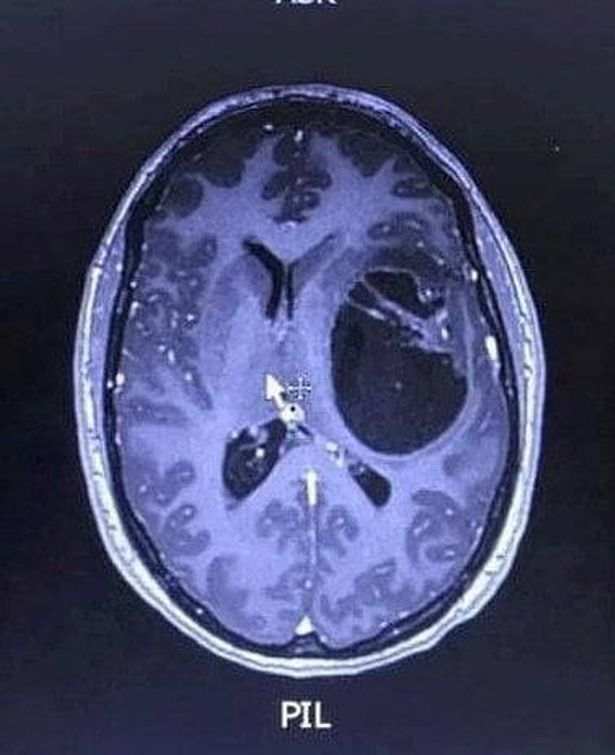

Following her collapse at work, Verity had initially thought her symptoms were caused by new medication she had begun taking for fibromyalgia – but her condition worsened and she was rushed to hospital. Scans revealed a mass on her brain, and she was transferred to Hull Royal Infirmary where surgeons drained excess fluid and took a biopsy which subsequently confirmed her brain cancer diagnosis.

In April 2022, Verity underwent a second operation where 89 per cent of her tumour was removed, followed by six weeks of radiotherapy and 12 months of chemotherapy. Three years on, the mum-of-four has surpassed her prognosis and quarterly MRI scans show her results remain stable.

“When the doctors showed us the scan and said there was a mass on my brain, we were devastated. Doctors told me that without treatment I could have just months to live – with treatment, maybe 12 to 18 months. It hit me like a tonne of bricks.”